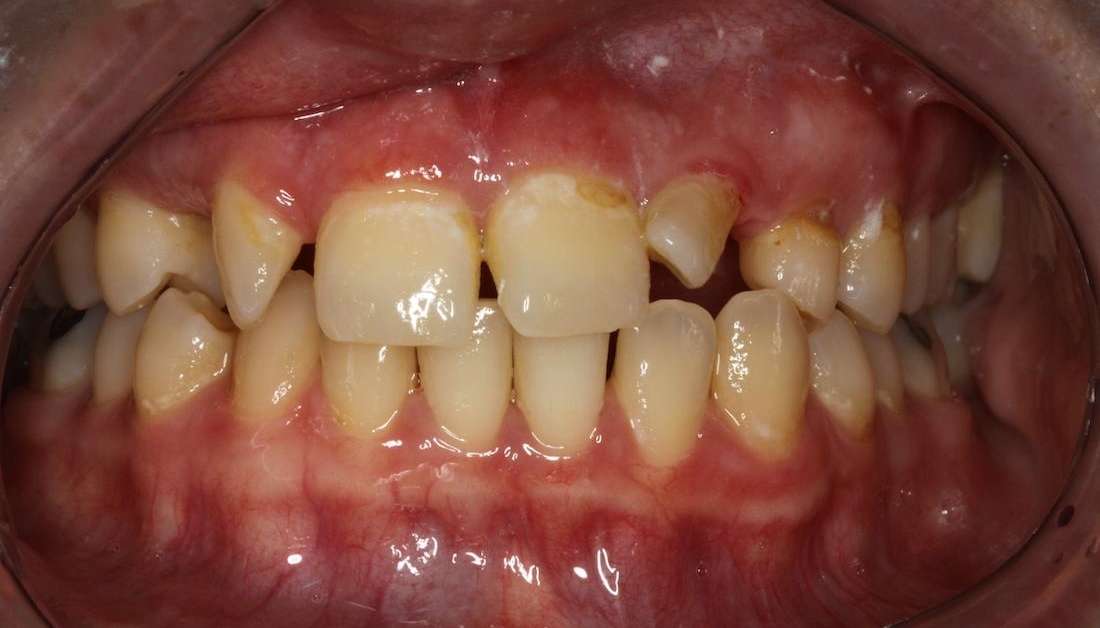

Bridge - Upper Front Teeth

This patient came to us unhappy with her smile. Dr. Mark created an anterior (front) bridge to help her have more uniform-looking teeth and stunning results.